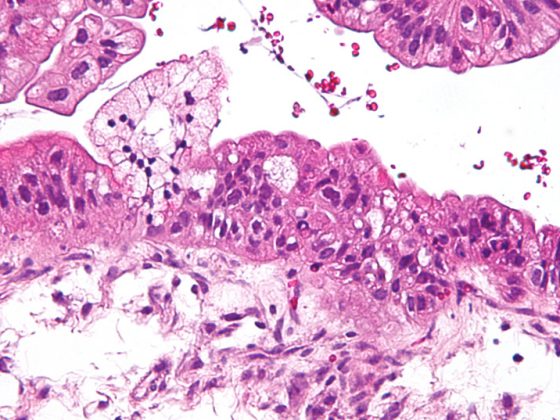

Das Stiefkind unter den entzündlichen Dermatosen

Die richtige Interpretation der Symptome dieser heterogenen entzündlich-intermittierenden Erkrankung ist klinisch bedeutsam. Eine mit Fehlbehandlungen verbundene Diagnoselatenz kann zu schwerwiegenden Komplikationen und einem hohen «Burden of disease» beitragen. Die Therapie erfolgt in Abhängigkeit vom Schweregrad der Erkrankung, wobei auch Komorbiditäten mitberücksichtigt werden sollten.